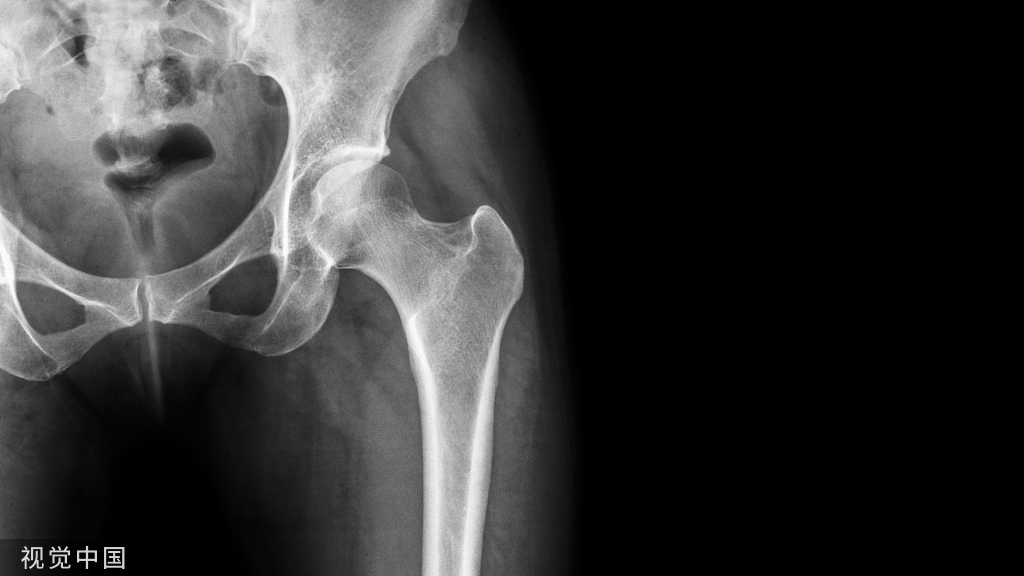

髋部骨折主要指髋臼骨折和股骨近端骨折,具体包括髋臼骨折、股骨头骨折、股骨颈骨折、股骨转子间骨折和股骨转子下骨折,其中股骨颈骨折和股骨转子间骨折是最常见的骨折类型。

老年髋部骨折常发生在股骨近端,主要包括股骨颈骨折与股骨转子间骨折,约占老年髋部骨折的90%以上

图1 股骨近端示意图a.股骨近端正位图;b.股骨近端侧位图